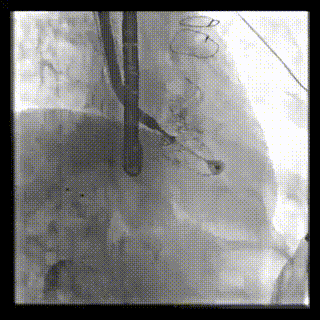

本周三例接受LuX-Valve Plus經(jīng)血管三尖瓣置換術(shù)的患者中,第一例患者為冠狀動(dòng)脈旁路移植術(shù)+Bentall+二尖瓣成形術(shù)后;第二例患者為永久起搏器植入術(shù)后,存在跨三尖瓣導(dǎo)線;第三例患者合并房顫、房缺及左心耳封堵術(shù)后。

三例患者入院后,葛均波院士團(tuán)隊(duì)周達(dá)新教授、潘文志教授、張?jiān)床┦俊㈥惿┦考靶某业呐舜湔浣淌?、李偉教授?duì)患者的情況進(jìn)行詳細(xì)評(píng)估和討論,最終決定為三例患者選擇LuX-Valve Plus40mm、50mm和50mm型號(hào)的瓣膜進(jìn)行手術(shù)治療。手術(shù)后即刻拔除氣管插管,術(shù)后患者三尖瓣反流癥狀得到顯著改善,復(fù)查心超結(jié)果顯示人工三尖瓣瓣膜支架固定穩(wěn)定,瓣葉關(guān)閉形態(tài)未見異常,未見明顯反流。